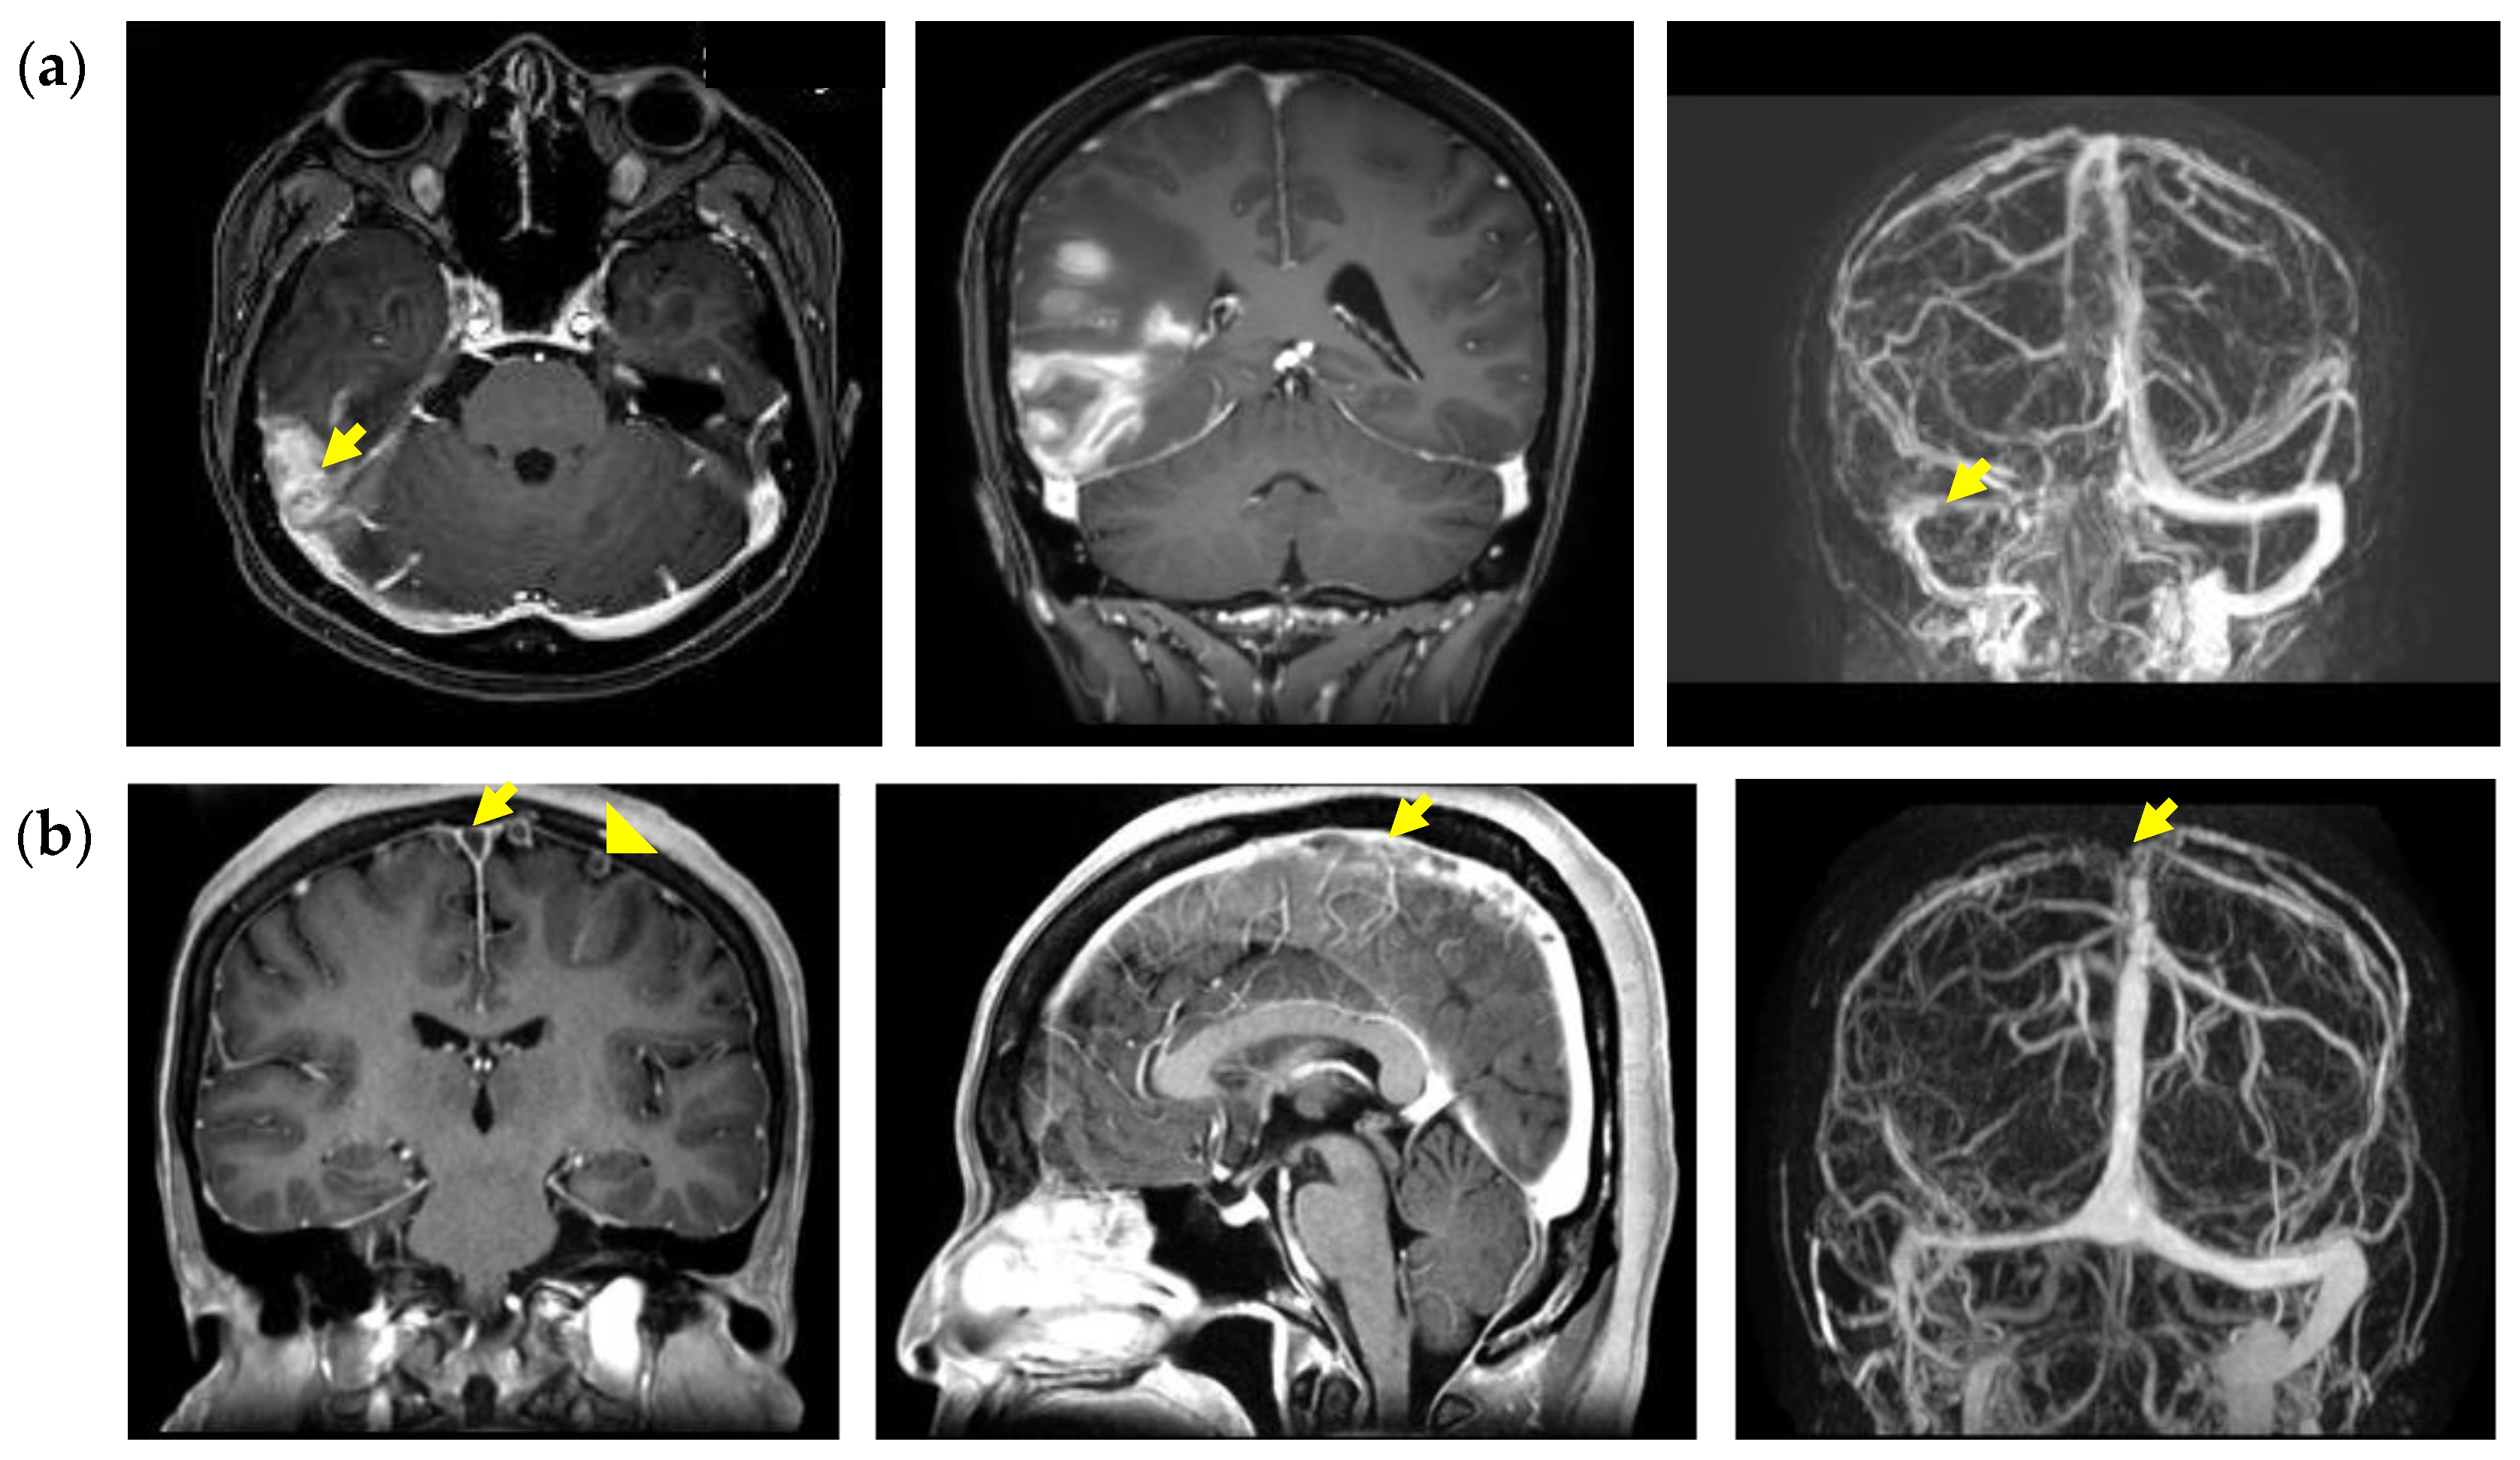

3.2. Clinical Presentations of Patients with Cerebral Venous Thrombosis